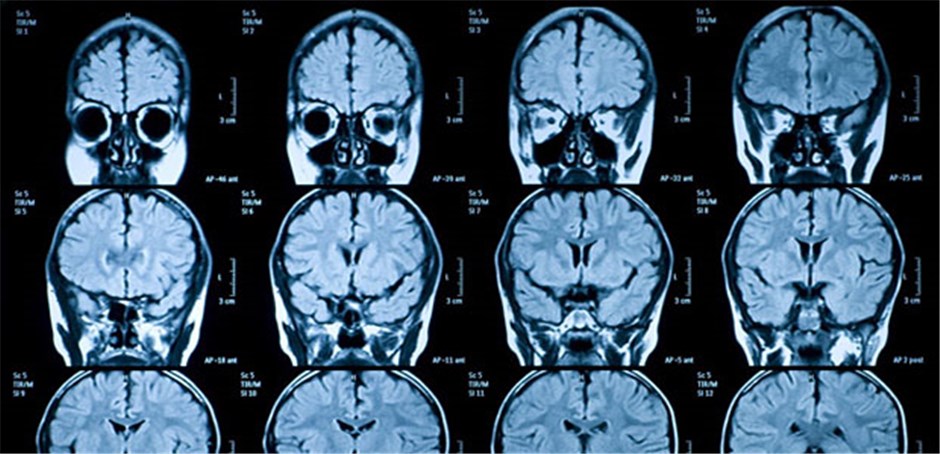

Die Magnetresonanztomographie (MRT), auch Kernspintomographie genannt, ist ein bildgebendes Verfahren, das keine Röntgenstrahlung verwendet. Stattdessen nutzt sie starke Magnetfelder und Radiowellen, um detaillierte Bilder vom Inneren des Körpers zu erzeugen. Im Gehirn ermöglicht die MRT die Darstellung von Strukturen wie dem Gehirn selbst, dem Rückenmark, Nervenbahnen und Blutgefäßen. Das Gerät erzeugt hochauflösende Bilder, die Ärzten helfen können, verschiedene Krankheiten und Verletzungen zu diagnostizieren. Es gibt verschiedene Arten der MRT, die für unterschiedliche Zwecke eingesetzt werden. Dazu gehören beispielsweise strukturelle MRT, funktionelle MRT (fMRT) und Diffusions-Tensor-Bildgebung (DTI). Jede dieser Techniken liefert unterschiedliche Informationen über das Gehirn.

Die strukturelle MRT erzeugt statische Bilder des Gehirns. Sie zeigt die Anatomie des Gehirns und kann verwendet werden, um Veränderungen in der Gehirnstruktur zu erkennen, wie sie beispielsweise bei Tumoren, Schlaganfällen oder Multipler Sklerose auftreten können. Sie kann auch Veränderungen im Volumen bestimmter Hirnregionen erkennen.